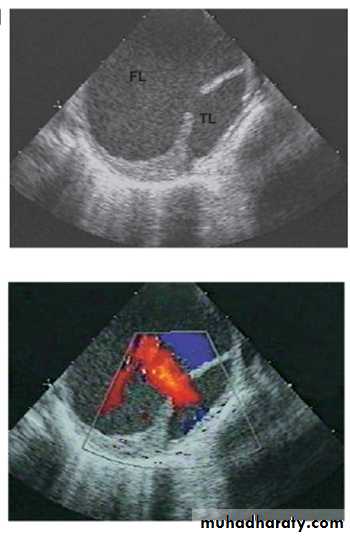

In this dramatic condition a breach in the integrity of the aortic wall allows arterial blood to burst into the media of the aorta which is then split into two layers, creating a 'false lumen' alongside the existing or 'true lumen'. The aortic valve may be damaged and the branches of the aorta may be compromised. Typically, the false lumen eventually re-enters the true lumen, creating a double-barrelled or biluminal aorta, but it may also rupture into the left pleural space or pericardium with fatal consequences.The primary event is often a spontaneous or iatrogenic tear in the intima of the aorta; multiple tears or entry points are common. On the other hand, many dissections appear to be triggered by a haemorrhage in the media of the aorta which then ruptures through the intima into the true lumen. This form of spontaneous bleeding from the vasa vasorum is sometimes confined to the aortic wall, when it may present as a painful intramural haematoma.

InvestigationsDoppler echocardiography may show aortic regurgitation, a dilated aortic root and, occasionally, the flap of the dissection. Transoesophageal echocardiography is particularly helpful because transthoracic echocardiography can only image the first 3-4 cm of the ascending aorta. CT and MRI are both highly specific, and angiography of the aortic arch is not usually required unless these techniques are not available.